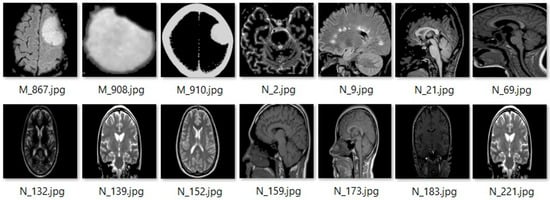

Topic-Modeling Guided Semantic Clustering for Enhancing CNN-Based Image Classification Using Scale-Invariant Feature Transform and Block Gabor Filtering

by Natthaphong Suthamno and Jessada Tanthanuch

J. Imaging 2026, 12(2), 70; https://doi.org/10.3390/jimaging12020070 - 9 Feb 2026

This study proposes a topic-modeling guided framework that enhances image classification by introducing semantic clustering prior to CNN training. Images are processed through two key-point extraction pipelines: Scale-Invariant Feature Transform (SIFT) with Sobel edge detection and Block Gabor Filtering (BGF), to obtain local [...] Read more.

This study proposes a topic-modeling guided framework that enhances image classification by introducing semantic clustering prior to CNN training. Images are processed through two key-point extraction pipelines: Scale-Invariant Feature Transform (SIFT) with Sobel edge detection and Block Gabor Filtering (BGF), to obtain local feature descriptors. These descriptors are clustered using K-means to build a visual vocabulary. Bag of Words histograms then represent each image as a visual document. Latent Dirichlet Allocation is applied to uncover latent semantic topics, generating coherent image clusters. Cluster-specific CNN models, including AlexNet, GoogLeNet, and several ResNet variants, are trained under identical conditions to identify the most suitable architecture for each cluster. Two topic guided integration strategies, the Maximum Proportion Topic (MPT) and the Weight Proportion Topic (WPT), are then used to assign test images to the corresponding specialized model. Experimental results show that both the SIFT-based and BGF-based pipelines outperform non-clustered CNN models and a baseline method using Incremental PCA, K-means, Same-Cluster Prediction, and unweighted Ensemble Voting. The SIFT pipeline achieves the highest accuracy of 95.24% with the MPT strategy, while the BGF pipeline achieves 93.76% with the WPT strategy. These findings confirm that semantic structure introduced through topic modeling substantially improves CNN classification performance. Full article